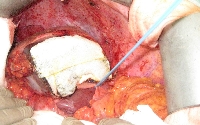

Πρόκειται για ασθενή 75 ετών που διαπιστώθηκε ότι έπασχε από αδενοκαρκίνωμα του σιγμοειδούς με 15 συνολικά ηπατικές μεταστάσεις αμφοτερόπλευρα (εικόνα 1). Η διενέργεια PET-CT δεν ανέδειξε εξωηπατική νόσο. Δεδομένου ότι η πρωτοπαθής εστία τέθηκε υπό προσωρινό έλεγχο με πολυπεκτομή, αποφασίστηκε η αντιμετώπιση πρώτα των μεταστάσεων ("liver first" approach). Με βάση τις εικονικές ηπατεκτομές κατά MEVIS (εικόνα 2) αποφασίστηκε η κάθαρση του ήπατος από το μεταστατικό φορτίο σε δύο στάδια (staged hepatectomy). Ο ασθενής υποβλήθηκε σε 6 κύκλους χημειοθεραπείας (Avastin, FOLFOX). Ακολούθησε δεξιά ηπατεκτομή (εικόνα 3). Κατόπιν υποβλήθηκε σε ακόμα 4 κύκλους χημειοθεραπείας. Η ογκομέτρηση την 4η μετεγχειρητική εβδομάδα ήταν ικανοποιητική (εικόνα 4). Ακολούθησε αριστερή πλάγια ηπατεκτομή (εικόνα 5), η οποία και έφερε την κάθαρση του ηπατικού μεταστατικού φορτίου. Η νέα ογκομέτρηση την 4η μετεγχειρητική εβδομάδα ήταν ξανά ικανοποιητική (εικόνα 6). Συνεχίστηκε η χημειοθεραπεία για ακόμα 4 κύκλους. Ακολούθως, ο ασθενής υποβλήθηκε σε σιγμοειδεκτομή. Τελικά, η χημειοθεραπεία ολοκληρώθηκε με άλλους 6 κύκλους. Ο ασθενής εξακολουθεί να παραμένει ελεύθερος νόσου στους τακτικούς ελέγχους (δις ετησίως) με κολονοσκοπήσεις και CT.